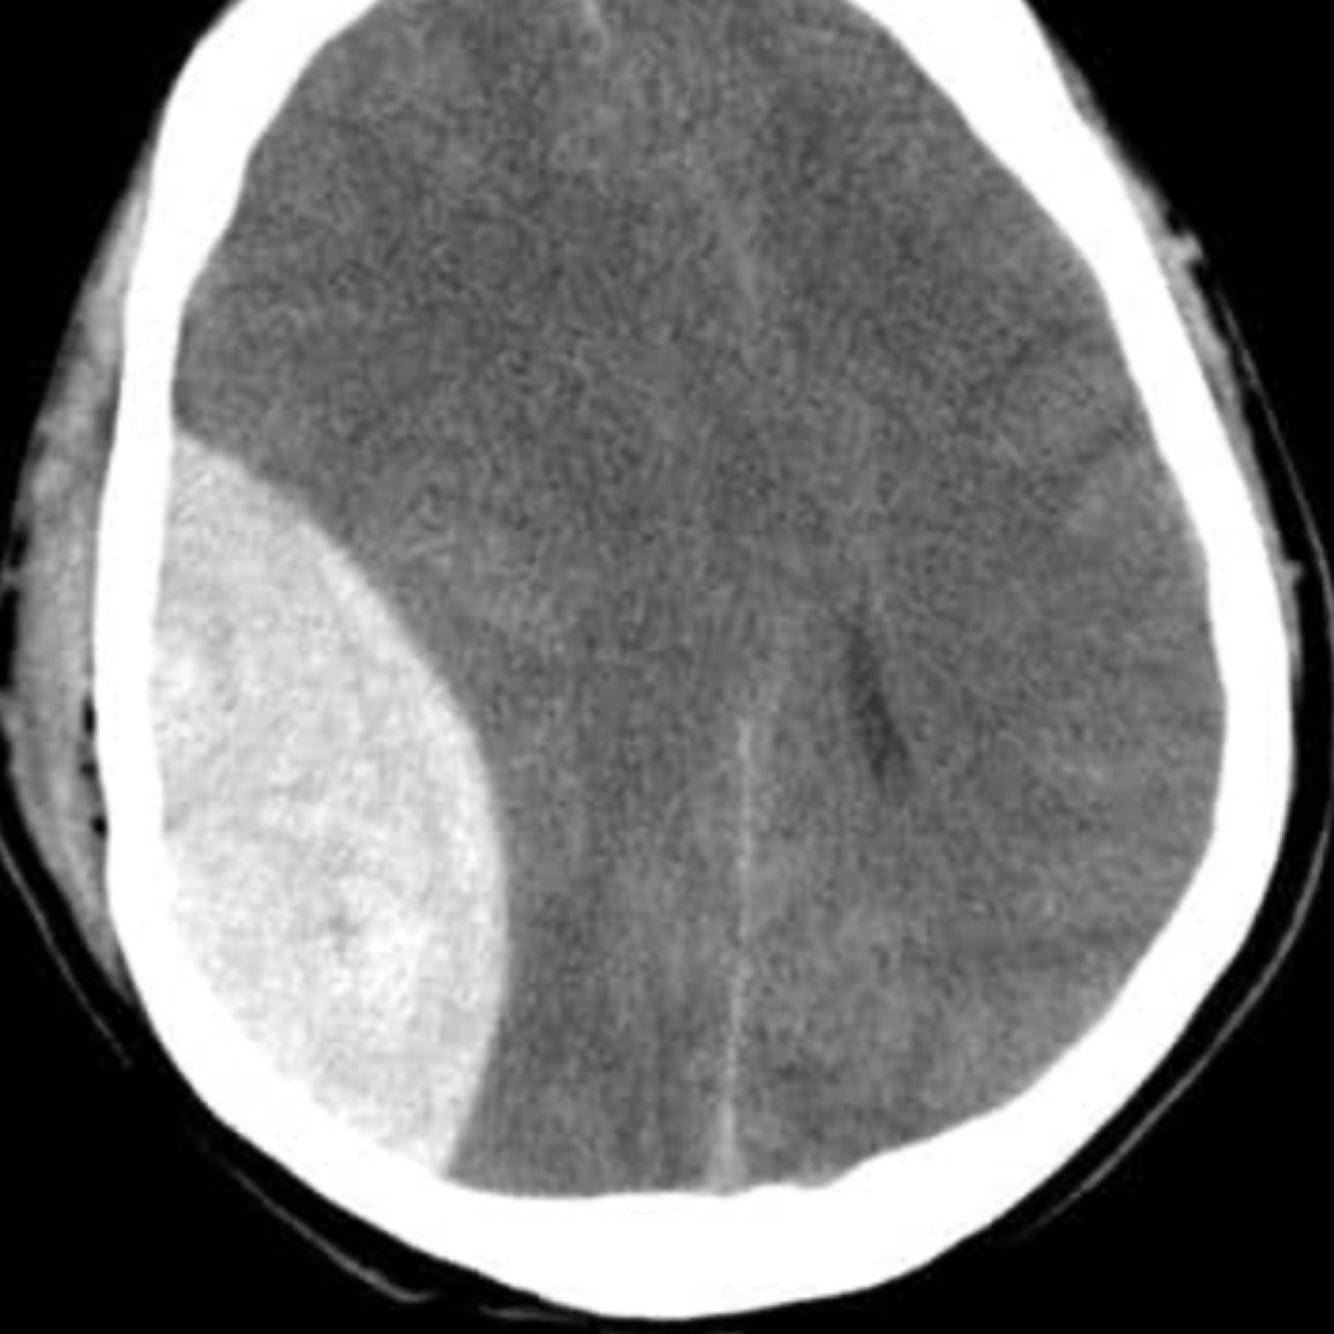

Subdural haemorrhage

This is a hemorrhage between the dura mater and arachnoid mater.

They may be acute, subacute, and chronic, but tend to present more gradually than extradural hemorrhages, with gradually increasingheadache and confusion.

They tend to occur in older patients.

Other risk factors include historic head trauma, alcoholism, and anticoagulation.

On CT, a crescent-shaped hematoma is diagnostic. This occurs as expansion of the haemorrhage is not limited by skull sutures, so follows the contour of the skull.

Neurosurgical intervention may be needed, if the haemorrhage is severe and symptomatic enough.

Acute subdural haemorrhage

Haemorrhage flows contour of skull as not limited by skull sutures

Subdural haemorrhage is caused by rupture of the bridging veins in the outermost meningeal layer. They occur between the dura mater and arachnoid mater. On a CT scan they have a crescent shape and are not limited by the cranial sutures (they can cross over the sutures).